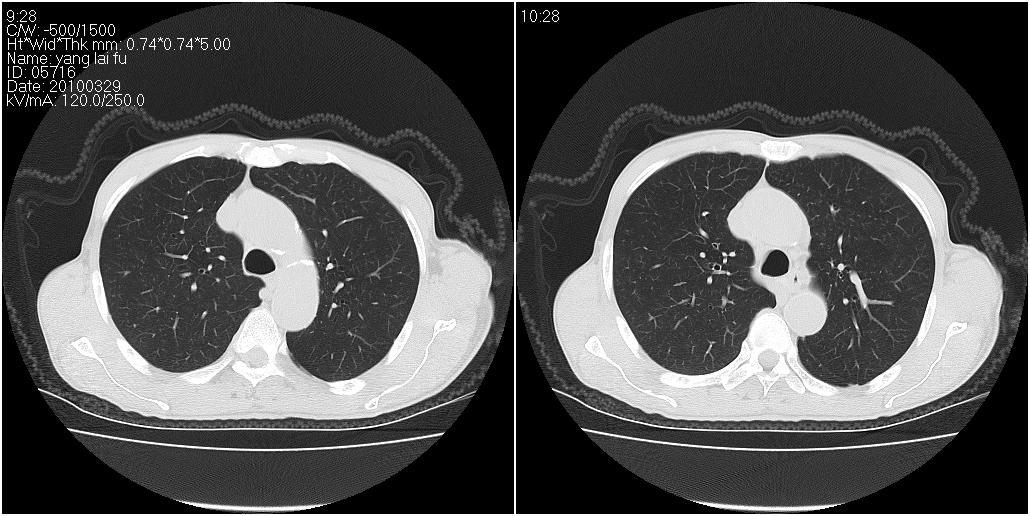

标题: CT25416:男性,70岁。胸片发现右下肺斑片状阴影 [打印本页]

标题: CT25416:男性,70岁。胸片发现右下肺斑片状阴影

以下是ct检查的情况:

考虑右肺下叶炎症可能性大?未除占位,建议增强。右下肺肺不张

右下胸壁皮下气肿。